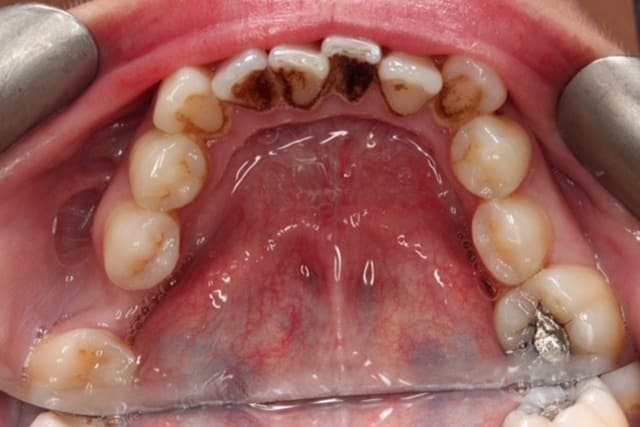

Dental Hygienist service after image – Bayswater Dental Clinic